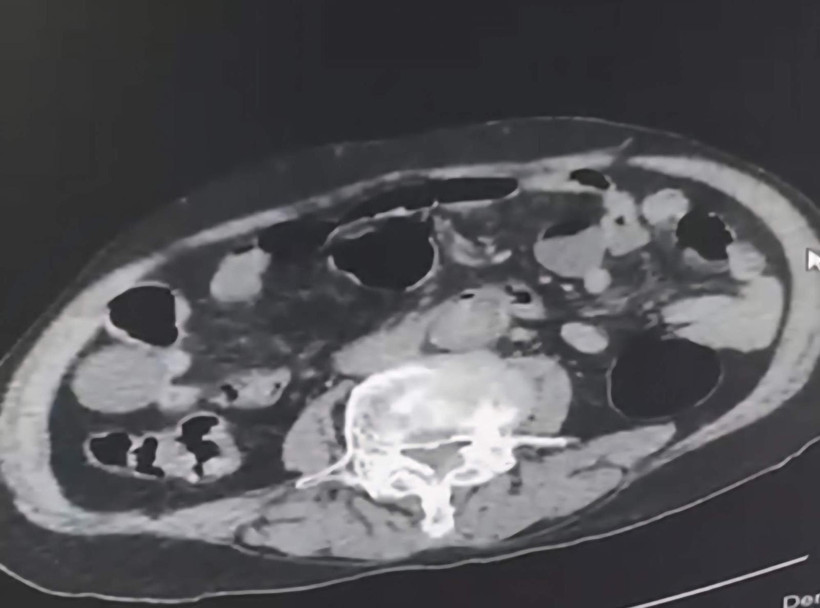

Gözaltına alınan şüpheliler üzerinde yapılan incelemelerde yabancı uyruklu bir şüphelinin uyuşturucu maddeyi cinsel organında taşıdığı belirlendi.